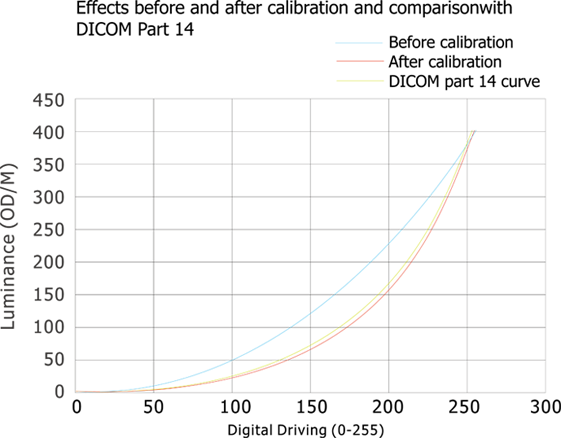

Conforme a la norma DICOM

Las imágenes médicas, incluyendo los detalles más sutiles, se pueden visualizar con precisión. Mantener la coherencia de visualización entre diferentes pantallas, así como la visualización y las diferentes modalidades de imágenes, garantizar la precisión del diagnóstico.